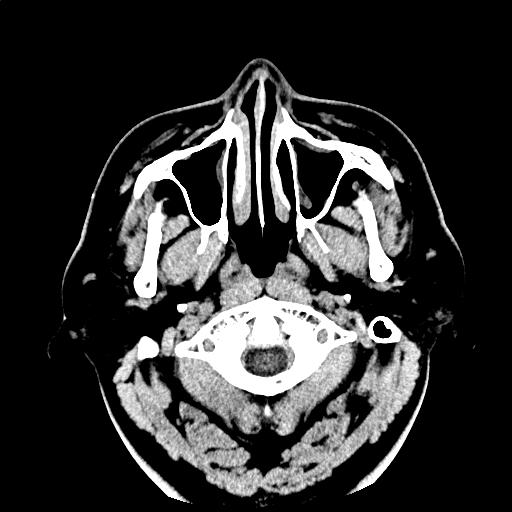

【読影指南】症例画像10

頭痛。ふらつき

年齢: 42歳

性別: 男性

検査部位: 頭部

検査種別: CT

CTスライス画像

CTスライス1